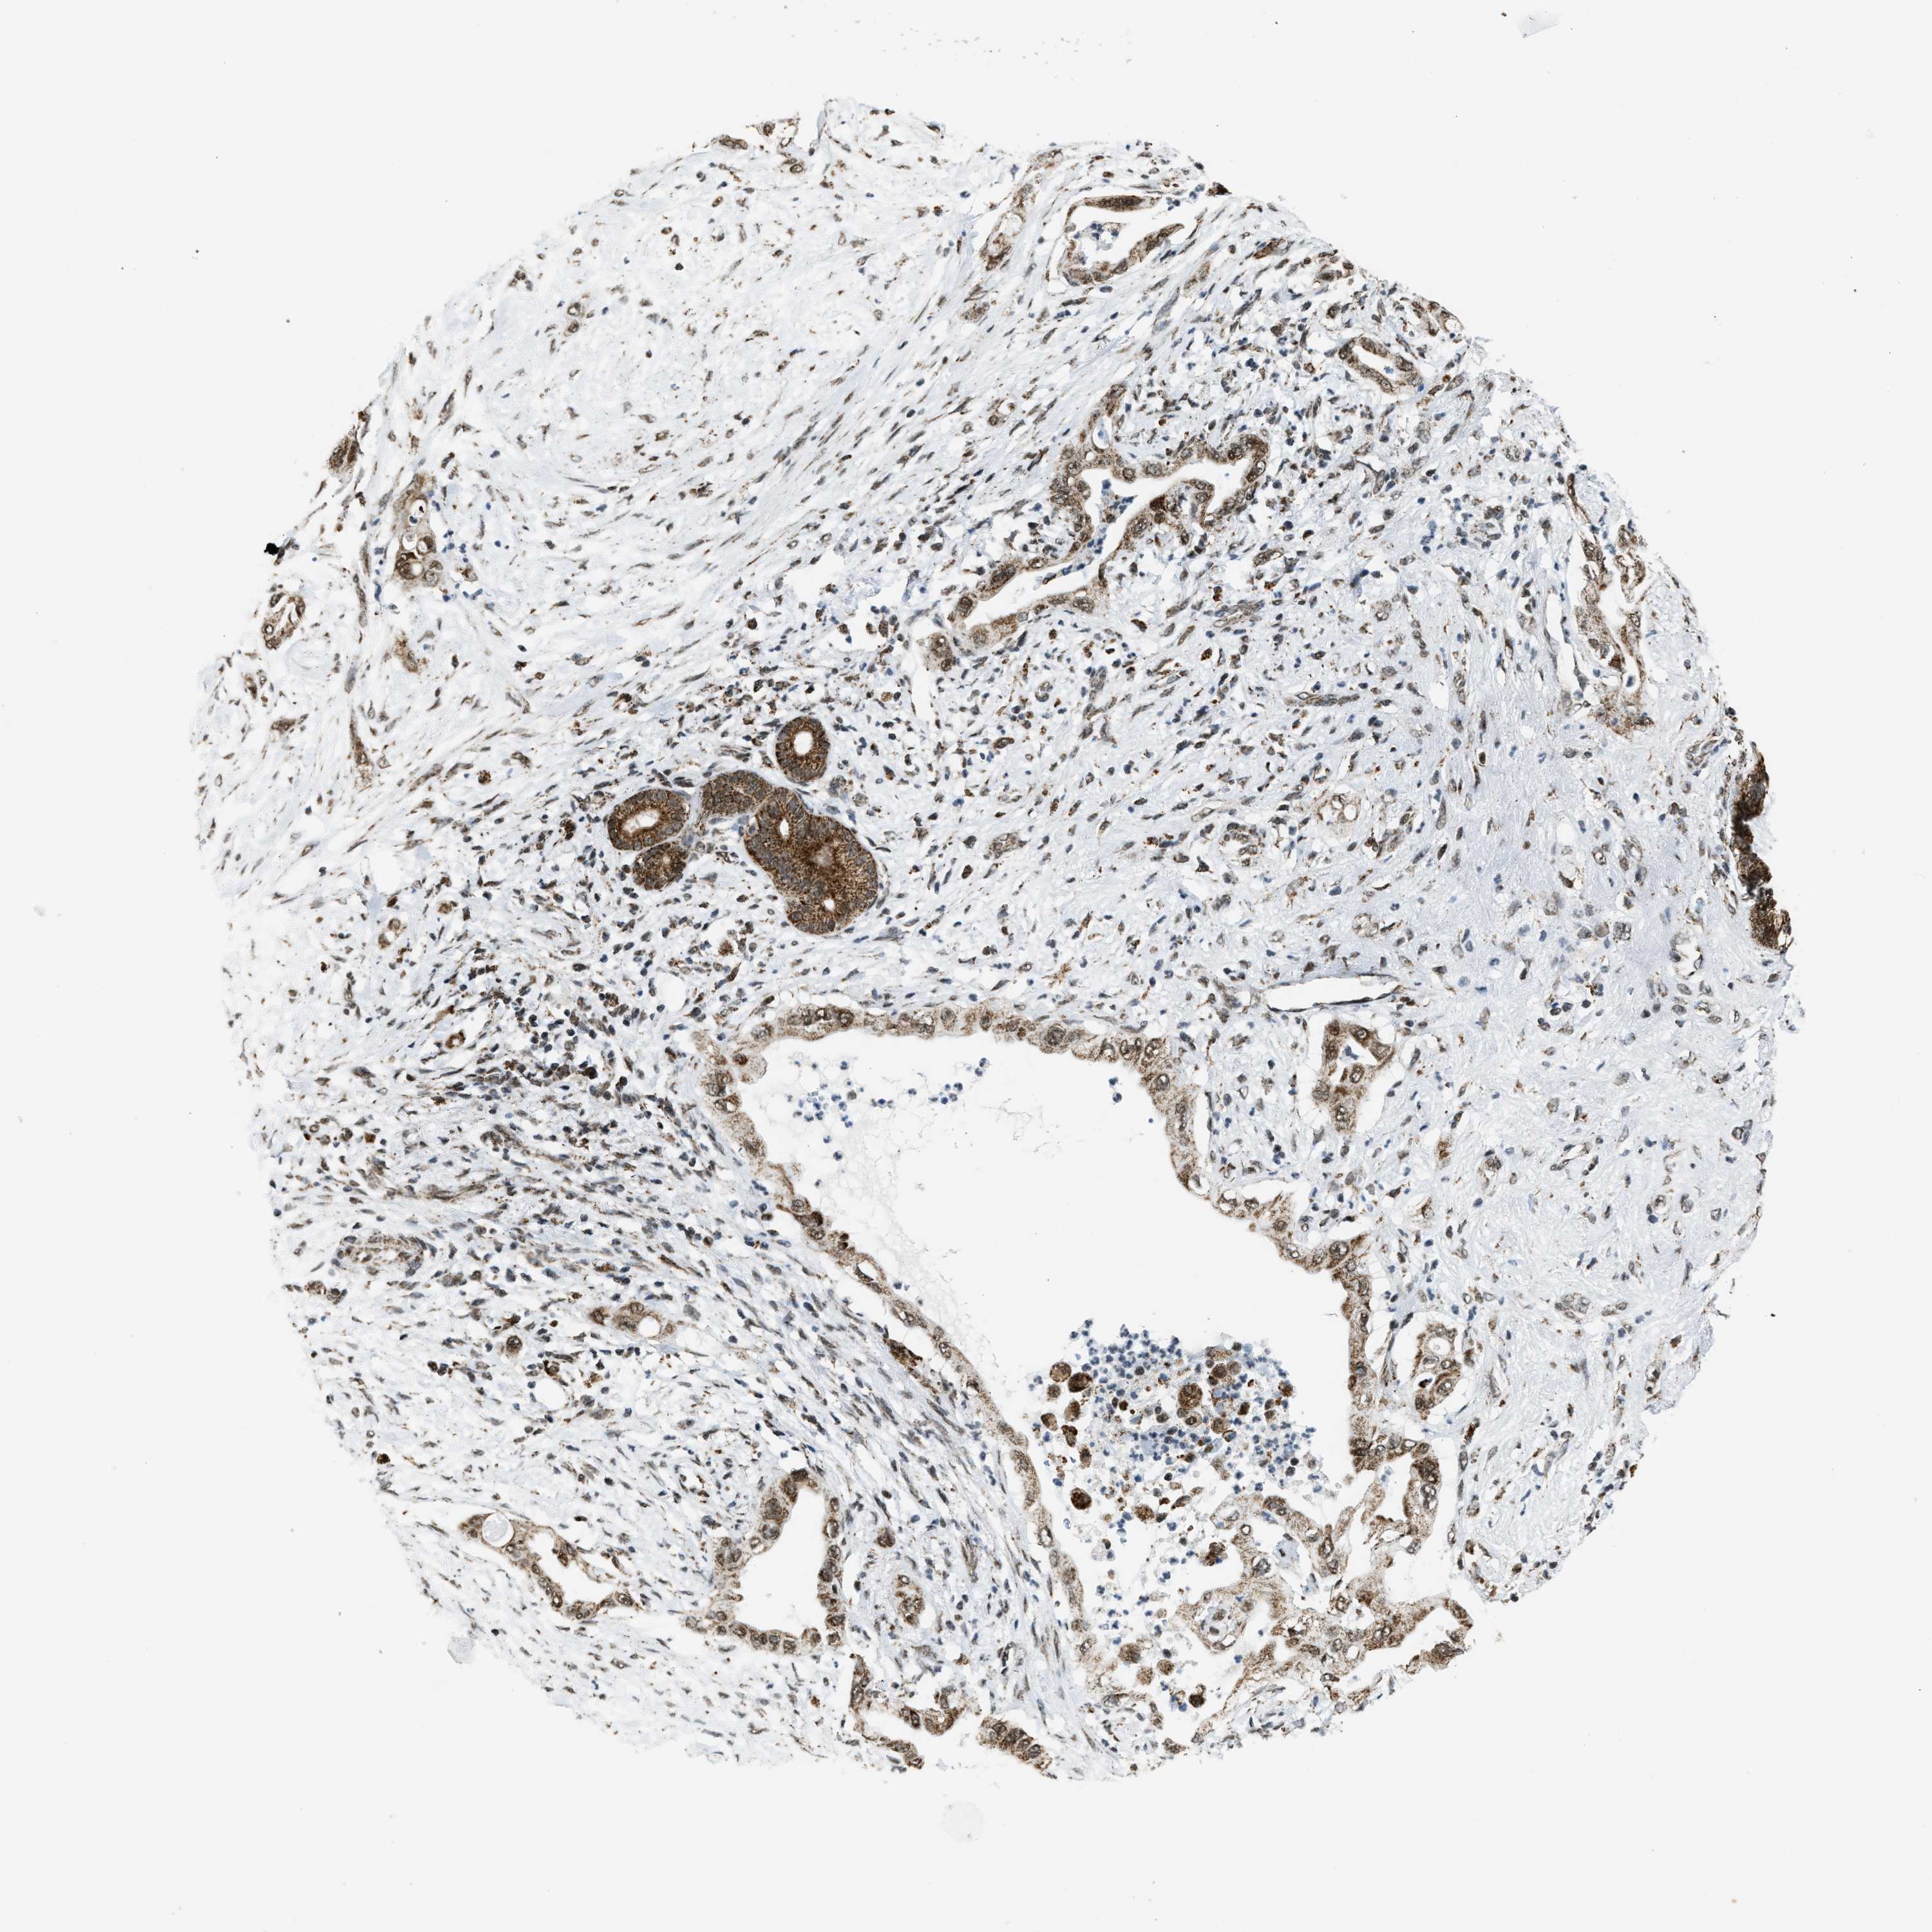

PANCREATIC CANCER - Protein expressioni

A mouse-over function shows sample information and annotation data. Click on an image to view it in a full screen mode. Samples can be filtered based on level of antibody staining by selecting one or several of the following categories: high, medium, low and not detected. The assay and annotation is described here.

Note that samples used for immunohistochemistry by the Human Protein Atlas do not correspond to samples in the TCGA dataset.

Antibody stainingi

Antibody staining in the annotated cell types in the current human tissue is reported as not detected, low, medium, or high, based on conventional immunohistochemistry profiling in selected tissues. This score is based on the combination of the staining intensity and fraction of stained cells.

Each image is clickable and will lead to virtual microscopy that enables deeper exploration of all samples and also displays staining intensity scores, fraction scores and subcellular localization as well as patient and tissue information for each sample.

Antibody HPA019522

Antibody HPA021002

Staining

High

Medium

Low

Not detected

Intensity

Strong

Moderate

Weak

Negative

Quantity

>75%

75%-25%

<25%

None

Location

Nuclear

Cytoplasmic/membranous

Cytoplasmic/membranous,nuclear

Adenocarcinoma, NOS